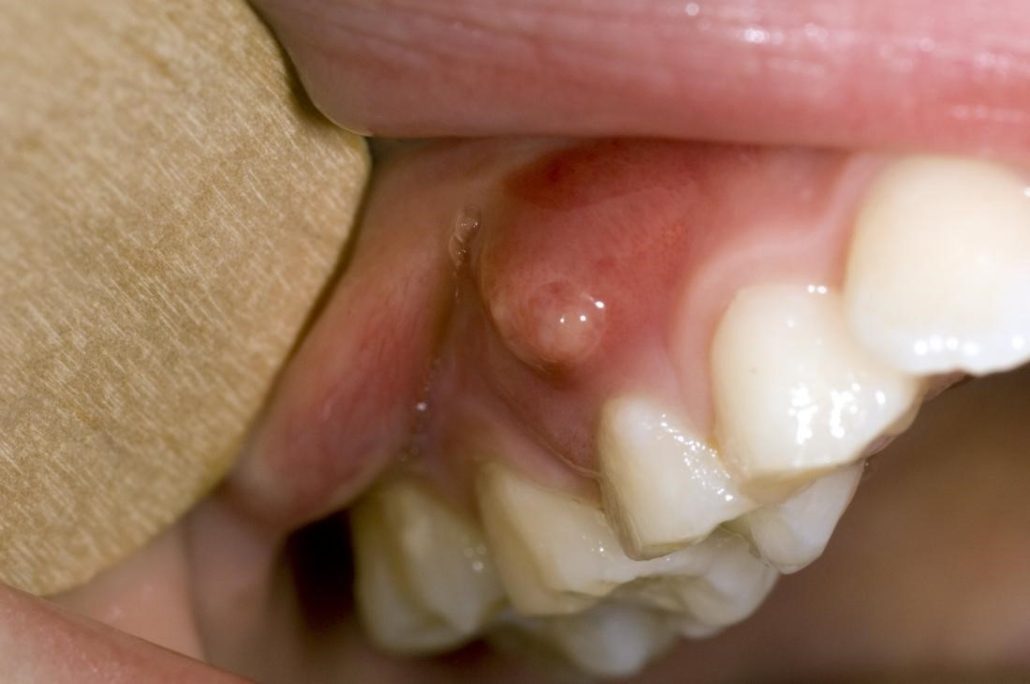

آبسه دندان یک زائده چرکی و عفونی است که در نتیجه عفونت باکتریایی ممکن است در قسمتهای مختلف دندان به وجود آید. این زائده عفونی می تواند تبعات مختلفی برای دندان فرد به وجود بیاورد که ساده ترین مشکل آن درد متوسط تا شدید است و در برخی موارد ممکن است این درد به قسمتهای دیگری مانند گوش یا گردن بیمار انتقال پیدا کند.

- آبسه جینجیوال (Gingival abscess): این آبسه روی لثه است.

با توجه به اینکه آبسه دندان خود را به صورت یک زائده عفونی و چرکی نشان میدهد تشخیص آن چندان سخت نیست، اما اصلی ترین علائم آن میتواند ملتهب شدن دندان ها و احساس درد در نزدیکی دندان و لثه باشد. درد ناشی از آبسه به طور ناگهانی افزایش می یابد و با گذشت زمان بدتر می شود. اما در عین حال علائم دیگری هم برای آن وجود دارد که شما می توانید به آنها استناد کنید:

- لثه های متورم و ملتهب